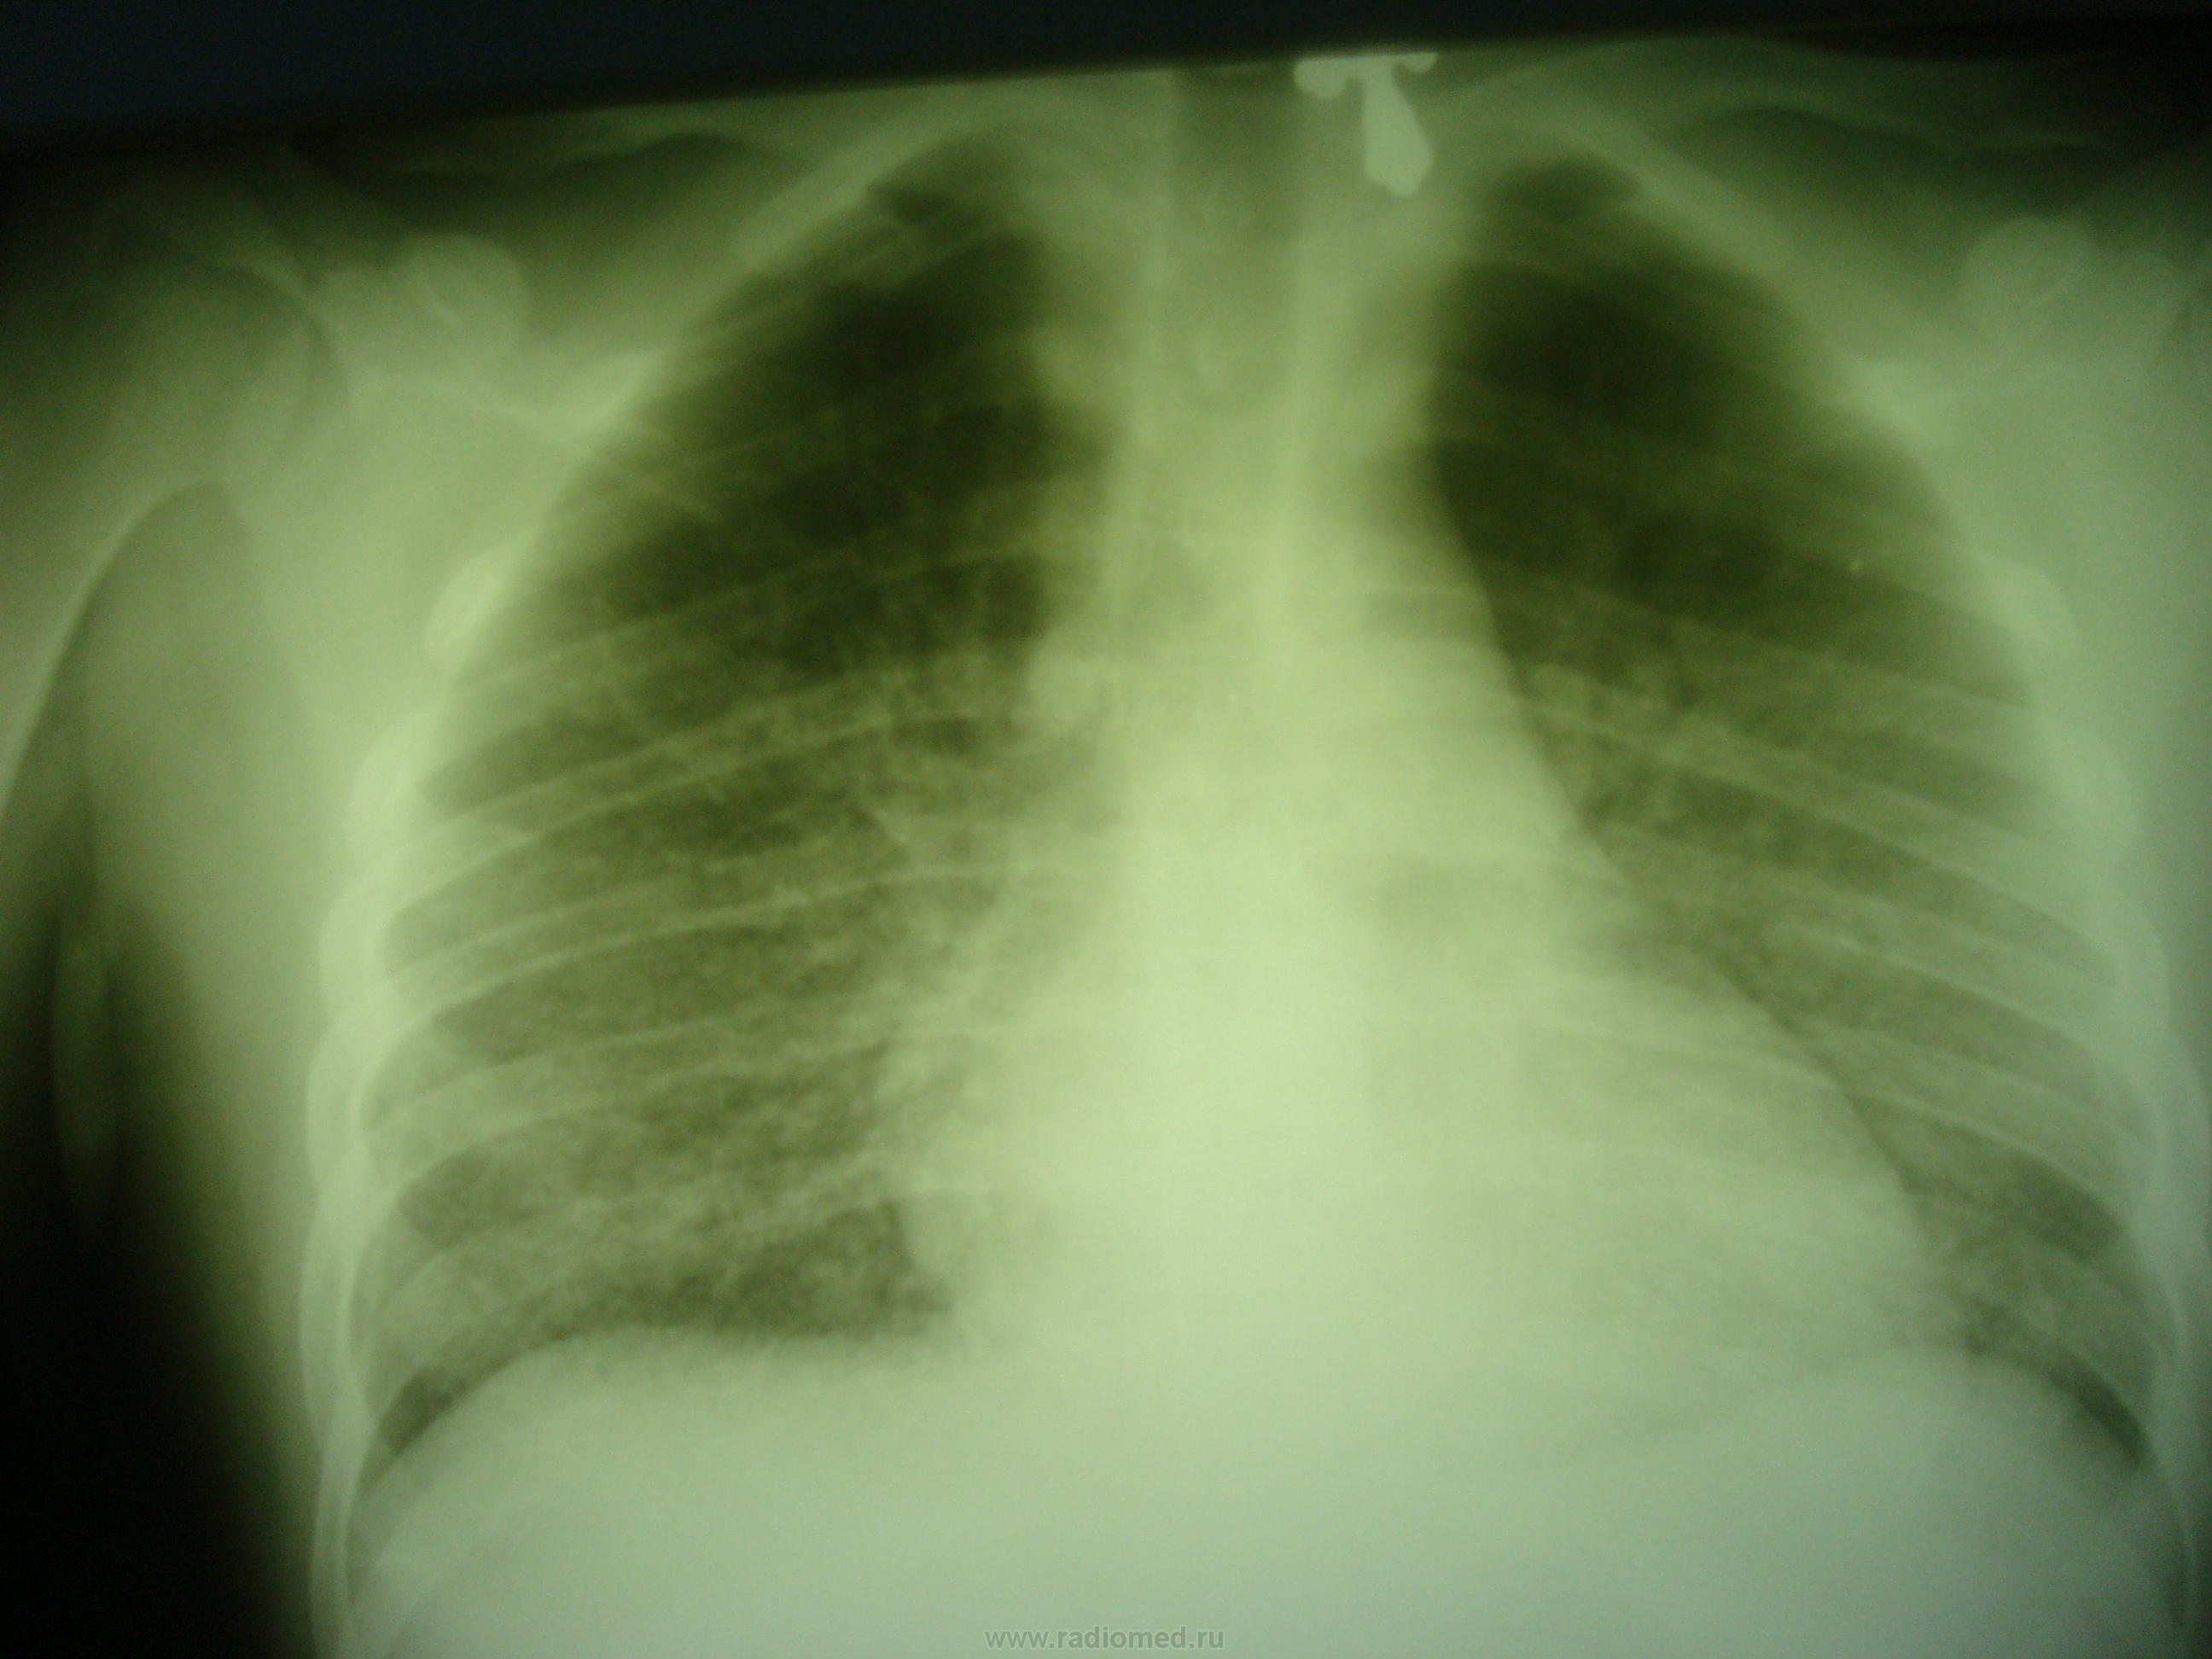

Пациент 21 год.Находился на лечении в гематолгическом отделении. DS Острый лейкоз.При поступлении в отделение 22..07.2013г выполенена R-грамма лёгких в прямой проекции.С 24.07.2013г появилсь лихорадка 38-39 градусов. 27.07 .2013года была выполена контрольная R-графия лёгких в 2-х проекциях. Состояние ухудшалось, появилась одышка 28.07.2013г. контрольная R-графия лёгких. Как можно расценить найденные в лёгих изменения?

связанная с лейкозом. Очаги и фокусы в легких определяются с обеих сторон в средних и нижних отделах с реакцией междолевой плевры.  Лечить основное заболевание и пневмонию. Не исключаю и лекарственное поражение легочной ткани.

Двустороннее усиление легочного рисунка за счет интерстициального компонента, мелкие очаги. Не исключено, что это лейкемоидные инфильтраты, особенно если бластов много в анализе крови

Как я понимаю, если кровь нестерильна-это уже сепсис.Есть ли на R-граммах признаки характерные для поражения лёгких при сепсие или всю R-семиотику можно объяснить проявлениями пневмонии? Или картину измений в лёгких можно трактовать как-то иначе? Дело в том, что как уже указывал выше, 28.07.2013г. на фоне лихорадки, состояние пациента ухудшилось, появилась нарастающая одышка, был переведён в реанимационное отделение, проводились реанимационные мероприятия, но несмотря на это, наступил летальный исход. Вскрытия не было ( обязательно  в таких случиях, бывает прижизненнное гистологическое подтвержение основного диагноза, методом стернальной пункции).

Если в крови гриб нашли, то при такой картине наверное была гематогенная диссеминация

Спасибо, за ссылку!yes Хоть и есть, как всегда, проблема языкового барьера (переводчик Google, не перевёл то, что в таблице, остальное перевёл грубовато, но суть ясна);  совсем по другому стал смотреть на представленный случай.У данного пациента, на фоне химиотерапии острого лейкоза, развилась иммуносупрессия, следствием которой, явилась септическая  грибковая ( кандидозая )пневмония, в виде милиарной диссеминации. Ну, где-то так, можно представить  патогенетическую цепочку исходя из статьи. Кончно если бы было КТ исследование лёгких  (как  это представлено в статье), информация по субстрату изменений лёгких была бы точнее.